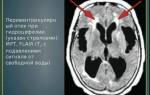

Перивентрикулярном регионы, особенно кзади вокруг треугольников, являются еще одним типичным расположением видных ПВП. В отличие от других областей, перивентрикулярные ПВП могут быть окружены гиперинтенсивным ободок на FLAIR в педиатрической возрастной группе. Это может отражать не полную миелинизацию белого вещества (то есть, терминальные зоны) или, возможно, спонгиозные изменения. В белом веществе, их ориентация, как правило, радиальная, отражая курс проникающих артерий в пределах паренхимы мозга. Нормальный диаметр ПВП не превышает 5 мм в нормальных условиях. Однако, известны случаи откровенной дилатации ПВП, что может иметь место в отсутствие любого патологического состояния как анатомический вариант. «Гигантские» ПВС может достигать 3 см в диаметре и их может быть трудно отличить от нейроэпителиальных кист на изображениях. Признание радиальной ориентации или прямой визуализации центральный на МРТ высокого разрешения является полезным для правильного диагноза. Иногда, расширение ПВП может быть распространено и вовлекает оба полушария головного мозга. Несколько патологических состояний могут быть охарактеризованы расширением ПВП. В педиатрической возрастной группе, это включает болезни накопления, такие как мукополисахаридозы (т.е. типы I и II). В этих расстройствах, блокирование ПВП, как полагают, приводит к накоплению аномальных материалов в ПВП. В таких случаях, ПВП расширение заметно включает в себя, кроме перивентрикулярного белого вещества — мозолистое тело. Таким образом, обнаружение нескольких каллозальных ПВС должна побудить метаболические исследования. Кроме того, ПВП могут предоставить маршрут для распространения ряд заболеваний, в том числе инфекции, воспаления, демиелинизация и опухоли.